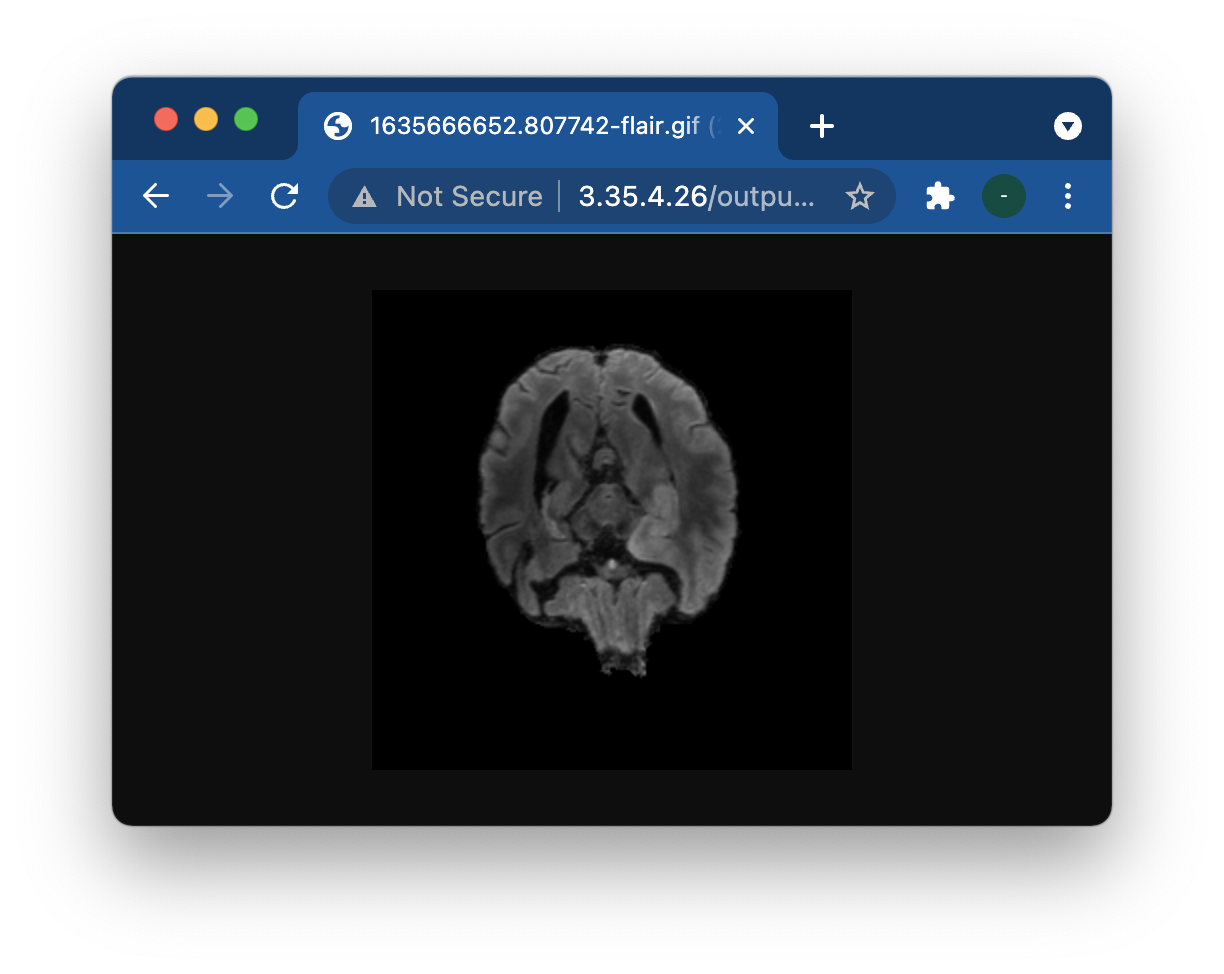

아래와같이 웹상에서 nii파일을 업로드하면, 이 파일을 서버로 보내서 결과물이 .gif형태로 아래 표시되는 웹사이트가 최종 구축 목표입니다.

그러면 잘 작동하는것을 볼 수 있습니다. 그러면 우리가 실제로 원하는 gif파일은

/home/ec2-user/server/static/output폴더에 있는데, 여기있는것은 잘 보일까요?

넵! 위와같이 잘 보입니다.

제 생각에는 "/output/1635666652.807742-flair.gif" 이렇게 http://[IP_ADDRESS]/ 이후의 경로만 잘 전달해주면 될것 같습니다.